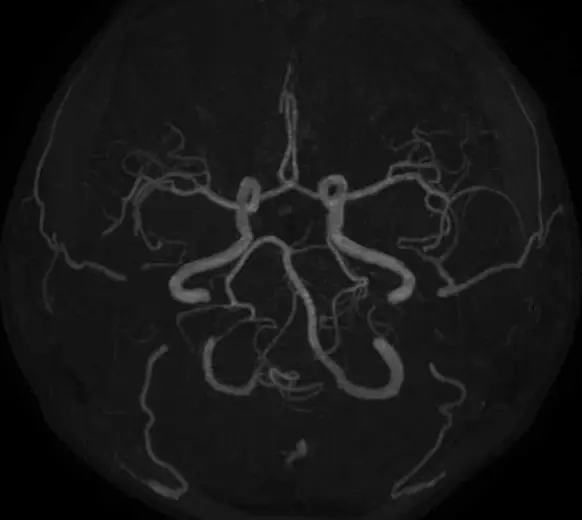

- 頭頸部領域、脳潅流イメージング(ASL)など